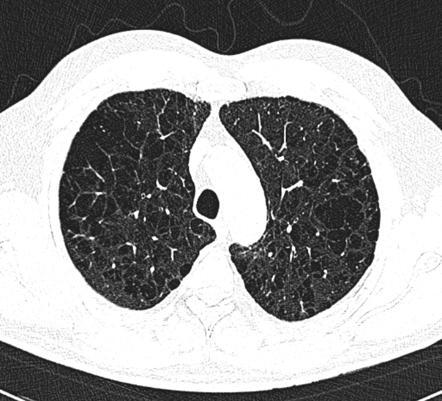

2. CT

고해상 CT로 X-ray를 통해서 못 보는 경증의 폐기종, 작은 기포, 폐기종의 종류를 알 수 있다.

경계가 불분명한 저음영과 얇은 벽을 가진 기포, 폐혈관음영의 감소 등을 볼 수 있다.